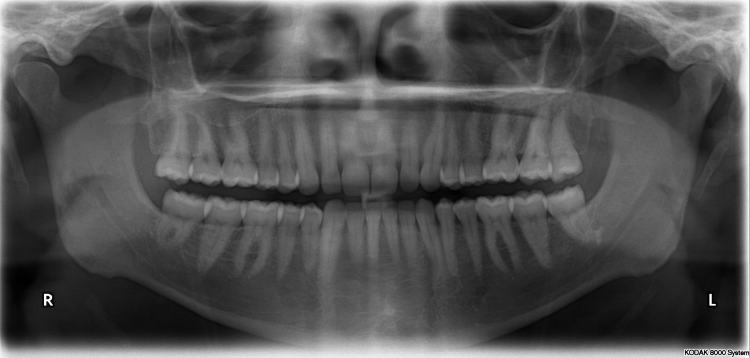

Panorámico

Una radiografía panorámica mostrará toda la boca de su hijo en una sola radiografía: todos los dientes tanto en la mandíbula superior como en la inferior. Estas radiografías se pueden usar para ver dientes emergentes, dientes impactados o tumores.